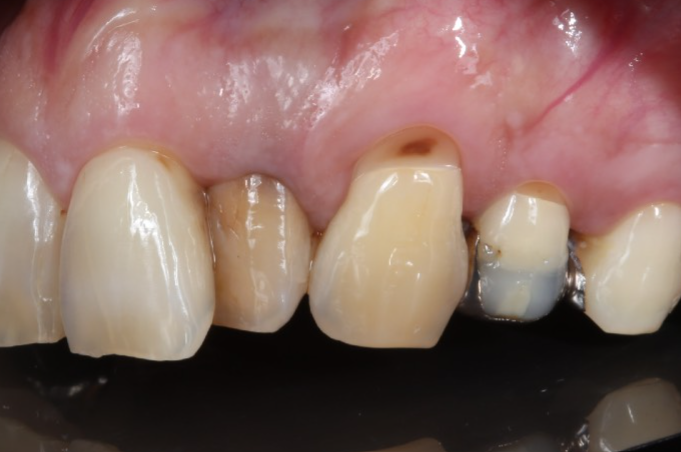

症例5

| 項目 | 詳細 |

|---|---|

| 患者様データ | 40代 男性 |

| 来院時の主訴 | 「歯が黒くなってきたのを治したい。冷たいものでしみる。」 |

| 医院の診断 | 左上側切歯は失活による変色 左上犬歯は非う蝕性歯頸部歯質欠損と歯肉退縮 左上第1小臼歯は銀歯による審美障害とう蝕 |

| 通院期間 | 3か月 |

| 来院回数 | 6回 |

| 治療費 | 総額:105,000円(税抜) 【内訳】 前歯ホワイトニング10,000円、歯頸部ダイレクトボンディング10,000円、セラミック治療85,000円・リスクと副作用:定期的なメインテナンスが必要・長期的には着色してくる可能性あり |

| リスクと副作用 | 定期的なメンテナンスが必要、術後若干の腫れと痛み |

| ここがこだわりのポイント!☝ | 歯肉退縮すると根面う蝕になりやすくなります。歯頸部のえぐれた歯肉退縮部位にCR充填し 歯磨きをしやすくすることで、根面う蝕の予防を目指しました。 |